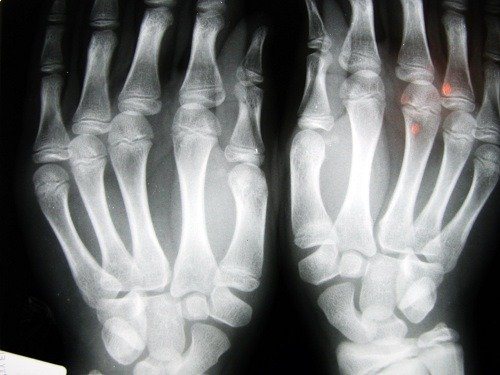

Η οστεοπόρωση είναι μια νόσος των οστών που προκαλεί μείωση της πυκνότητας της οστικής μάζας. Η νόσος αυτή χαρακτηρίζεται από πορώδη οστά. Επειδή αυξάνεται το μέγεθος των εσωτερικών κυττάρων των οστών, αυτά γίνονται εύθραυστα και σπάνε πιο εύκολα.

Συχνά παρουσιάζονται κατάγματα στους καρπούς, καθώς και στη σπονδυλική στήλη ή στον γοφό. Πρόκειται για το πιο σοβαρό κάταγμα, επειδή απαιτεί άμεση χειρουργική επέμβαση και έχει σοβαρές συνέπειες για τη ζωή των ασθενών.